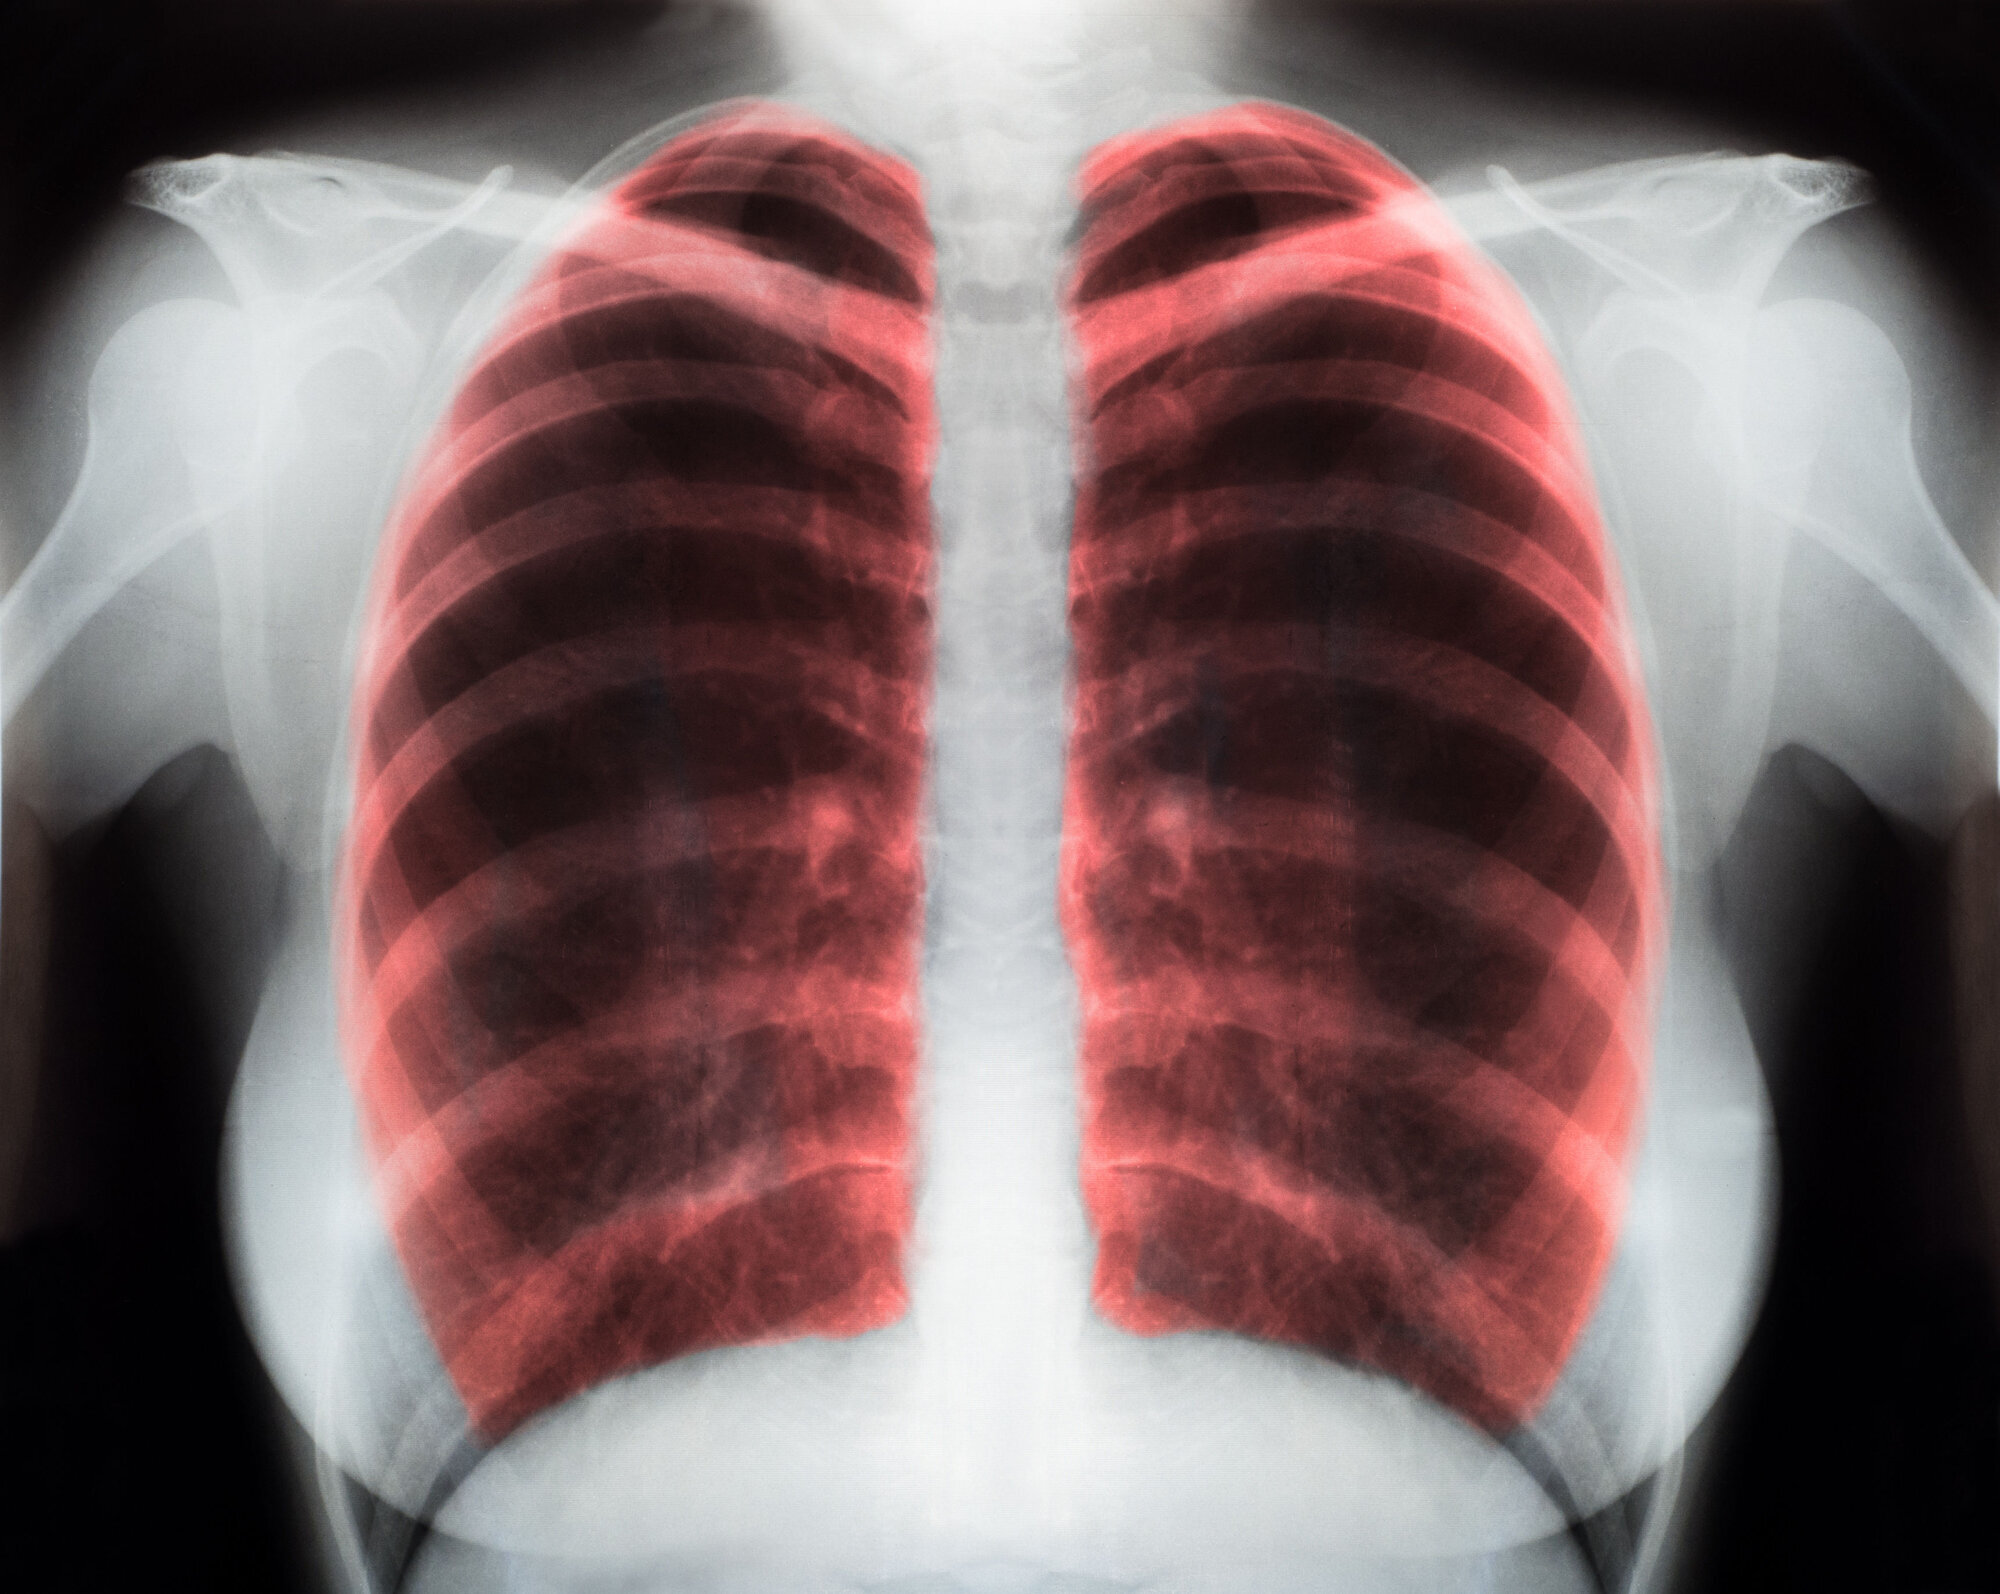

Kronisk obstruktiv lungesykdom (kols) som har fått utvikle seg til en alvorlig grad av sykdommen, vil påvirke pasientenes livskvalitet negativt med høy symptombyrde. Pasientene strever særlig med å puste, noe som begrenser deres daglige aktiviteter. Tidligere studier har vist lovende resultater ved å anvende telemedisinsk oppfølging av kolspasienter.